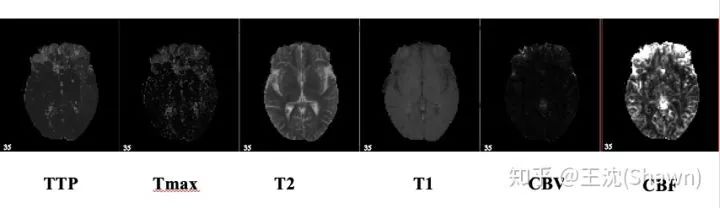

3.多模态。相比自然影像,医疗影像比较有趣和不同的一点是,医疗影像是具有多种模态的。以ISLES脑梗竞赛为例,其官方提供了CBF,MTT,CBV,TMAX,CTP等多种模态的数据。

这就需要我们更好的设计网络去提取不同模态的特征feature。这里提供两篇论文供大家参考。